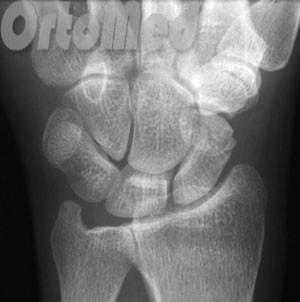

Диагностика переломов ладьевидной кости

Очень важно диагностировать перелом ладьевидной кости как можно раньше, поскольку значительная часть ладьевидной кости имеет плохое кровоснабжение и перелом может не срастись, или наступить некроз фрагмента кости (некровоснабжаемый фрагмент погибает), а это ведет к серьезным отрицательным последствиям (ограничение движений в лучезапястном суставе).

Первым и обязательным диагностическим моментом является рентгенография поврежденного участка конечности. Чаще всего рентгенография ясно показывает характер перелома ладьевидной кости.

В некоторых случаях, когда по рентгенограмме тяжело определить соотношение отломков назначается компьютерная томография лучезапястного сустава. При таком исследовании можно трехмерно увидеть поврежденную кость, что поможет в определении тактики оперативного лечения перелома.

Если перелом ладьевидной кости происходит без смещения отломков, то линию перелома на рентгенограмме можно и не увидеть. Поэтому очень важно при любой травме кисти выполнить шинирование на 10 дней. На 10 день повторить рентгенограммы кисти и, если перелом все же был, он станет четко просматриваться. Ну а далее выполняют соответствующие лечебные мероприятия (см. раздел лечение переломов ладьевидной кости).